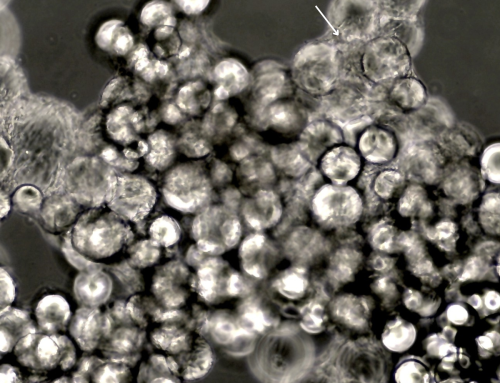

In a recent study, researchers successfully differentiated iPSCs into CECs by first transforming them into neural crest cells (NCCs), a precursor stage in normal CEC development. These iPSC-derived CECs displayed the typical hexagonal structure and expressed critical markers—ATP1A1 and ZO-1—that are essential for CEC function. These markers enable the pump and barrier actions needed to maintain corneal clarity, suggesting that the iPSC-derived cells could perform similarly to native CECs.

- Stable Integration: Immunohistochemical analysis confirmed that the transplanted cells integrated well into the corneal tissue, maintaining expression of essential CEC markers such as ATP1A1 and ZO-1.